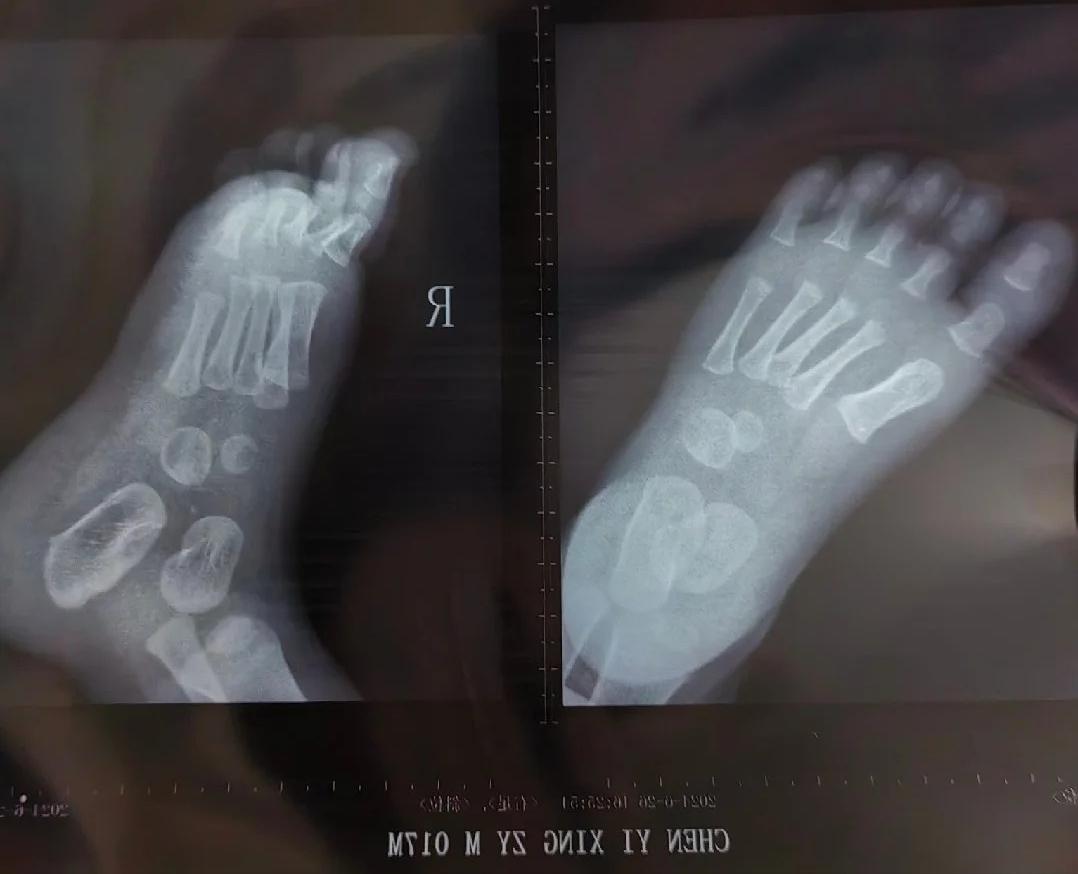

人类幼崽手部的X光照片,看起来骨头都不是连在一起的 其实中间的那些“空隙”,并非什么都没有,而是X光拍不出来的软骨组织,也被称为骨骺线。 手部X光照片,也是确定孩子“生物学”年龄的最可靠方法之一,也就是我们常说的“测骨龄”。 通过腕部的骨骺线,可以判断孩子是否早熟,还有没有长高的空间。 #你知道吗#